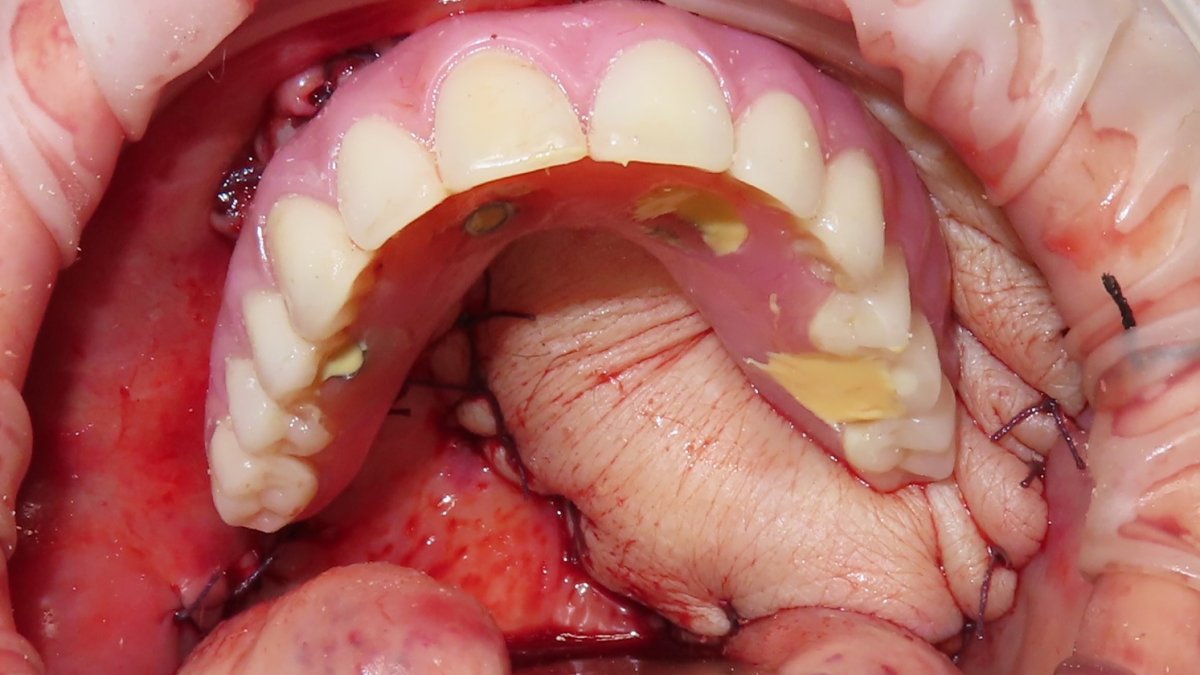

Perforated flap